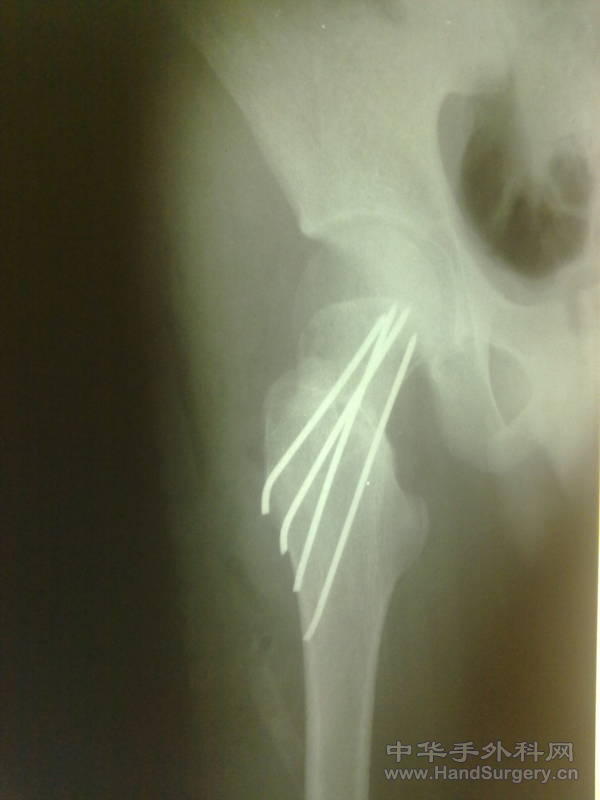

发一例股骨颈骨折

患者17岁,外伤致股骨颈骨折,请大家看看是否有更好的固定方法。

为什么用克氏针而不用空心螺钉啊?

股骨颈骨折用克氏针内固定,真是第一次见到.唉?

原则上是应该行空心钉内固定,估计作者想减少对骺板得损伤吧。

用克氏针固定股骨颈,患者术后要卧床多久啊!经典固定方法,强人!用克氏针,竟然用克氏针。。。。。。。。。

年青人,如为这种骨折很多是高能量损伤,坏死率比老人更大,再加上这种处理,我想也就差不多了,这伤还是按原则来吧,三枚双头空心加压,呈品字固定。术后尽量晚负重。